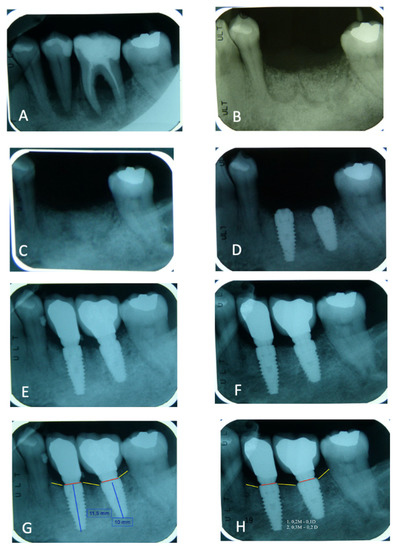

3.1. Peri-Implant Bone Loss Evaluation

3.4. Peri-Implant Bone Loss